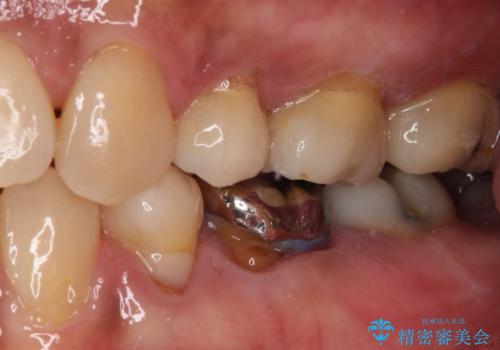

- 矯正治療後に、下顎奥歯の銀歯をすべてゴールドにすることを希望された患者様です。

セラミッククラウンやセラミックインレーによる補綴治療も提案しましたが、お友達にゴールドを自慢したいとのことで、ゴールドクラウンとゴールドインレーにて処置することとしました。